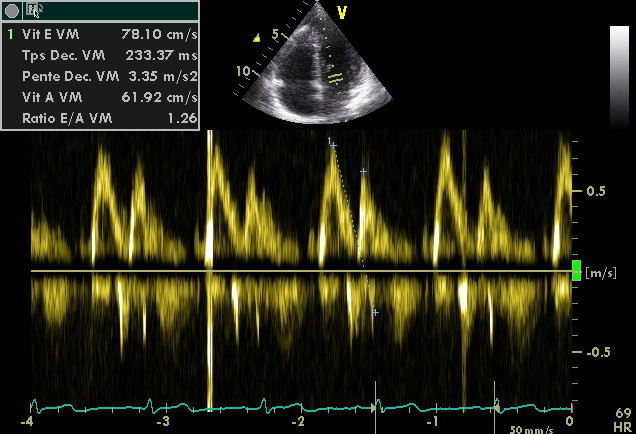

Enregistrement du flux transmitral en Doppler pulsé